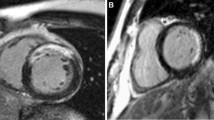

CMR-LGE protocols

Patients were examined in the supine position using a 1.5-T imaging unit (Signa Infinity Twinspeed, General Electric Healthcare, USA) equipped with master gradients (30 mT/m peak gradients; 150 mT/m/ms slew rate) and a 5-element cardiac phased-array receiver coil. Images were obtained using electrocardiographic gating and expiratory breath holds. A dose of 0.2 mmol/kg of body weight of gadopentetate dimeglumine (Magnevist; Bayer Schering Health Care, Cambridge, UK) was administered intravenously at a rate of 5 ml/s with a power injector. Ten minutes after contrast agent injection, a Look-Locker sequence was performed to obtain the most appropriate inversion time to nullify the signal intensity of normal myocardium. The left ventricular short-axis imaging layer was 8 mm thick and 0 mm apart. The left ventricular 2-chamber and 4-chamber scanning imaging layers were 5 mm thick and 0 mm apart. This was immediately followed by the acquisition of LGE images, with an inversion recovery prepared T1-weighted gradient-echo sequence (4.9/1.9; flip angle, 15 degrees; turbo field-echo factor, 30; spatial resolution, 1.35 × 1.35 × 10 mm). Late gadolinium enhancement was interpreted as present or absent by the consensus of two CMR-trained physicians, and was considered present only if confirmed on both short-axis and matching long-axis myocardial locations.

First, we marked the segments of the myocardial scar with the bull’s eye segmental comparison (17-segment model) and compared them with the results of coronary angiography. Second, we searched for the thickest myocardial scar layer-by-layer on the short axis imaging and calculated the percentage of the thickness of the myocardial scar, which was defined as a transmural myocardial scar when the percentage was > 75%, according to previous study [13]. Beek et al. demonstrated that the transmural extent is relevant in predicting myocardial functional recovery: The likelihood of complete functional recovery of segments without LGE was 3.8, 11.1, and 50 times higher than that of segments with 26–50%, 51–75%, and > 75% LGE, respectively (P < 0.001) [13]. Finally, we recorded the area of myocardial scar and calculated the percentage of myocardial scar volume by segment software.

Myocardial scars were diagnosed in 41 of 42 STEMI patients (96.7%) by using CMR-LGE. A patient-by-patient visual analysis of scar tissue location in the STEMI group, with bull’s eye segmental comparison of CMR-LGE findings is shown in Additional file 1: Fig. S1. In all patients, the anatomic locations of scars defined by CMR-LGE corresponded to the distributions of the culprit vessels treated with primary angioplasty. For example, in a patient with angiographically proven left anterior descending coronary artery occlusion, CMR-LGE indicated scarification of the basal and middle segments of the left anterior ventricular wall. In another patient with right coronary artery occlusion, CMR-LGE disclosed a scar that involved the entire inferior wall of the left ventricle and the middle and apical segments of the posterior interventricular septum (Additional file 1: Fig. S2). However, scar size and thickness were unrelated to the degree of coronary artery occlusion. Stenoses in all culprit arteries exceeded 90%; nonetheless, there were significant inter-patient differences in scar size and thickness (P < 0.001).